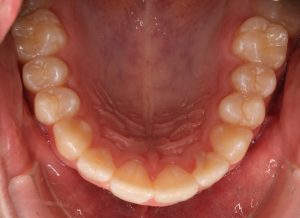

* 2 zgornja in spodnja retencijska žička

*2.Retencijske žičke so v uporabi od leta 1970. Fiksacija zob z retencijsko žičko, ki je nalepljena na notranji strani zob, se je izkazala za zelo priljubljeno, saj prepečeuje premike zob, kjer je recidiv zelo verjeten in snemni retencijski aparati niso zanesljivi, prav tako ni potrebno pacientovo sodelovanje. Po množični in dolgotrajni uporabi pa se je izkazalo, da te žičke niso tako nedolžne in lahko pride do stranskih neželjenih učinkov.

Leta 2022 je bila narejena prva študija o stranskih učinkih retencijske žičke. V ortodonstkih krogih je pojav dobil ime WIRE-SINDROM. Nov pojem wire sindrom se nanaša na premike zob, ki jih je mogoče opredeliti kot nenormalne, nepričakovane, nepojasnjene ali prekomerne premike zob, ki jih še vedno drži nepoškodovana ortodontska retenerska žica brez odstopitve ali zloma, kar vodi do razvijajočih se estetskih in/ali funkcionalnih posledic, tako zobnih kot parodontalnih.

Primer iz naše ambulante

Wire sindroma je nov pojav in je zaskrbljujoč za ortodonte, splošne zobzdravnike in parodontologe predvsem pa za paciente. Pomembno je, da primere odkrijemo zgodaj in se takoj učinkovito preprečijo nadaljni neželeni premiki zob in z njimi povezane posledice za dento-parodontalno tkivo ter se odločimo za ustrezno terapijo. Sporočilo akademske stroke pa je, da so potrebne dodatne klinične študije za razjasnitev etiopatogenih mehanizmov žičnih sindromov in njihovih kliničnih vplivov, kar bo akademski stroki na koncu omogočilo, da kliničnim ortodontom predlagajo učinkovite preventivne ukrepe.